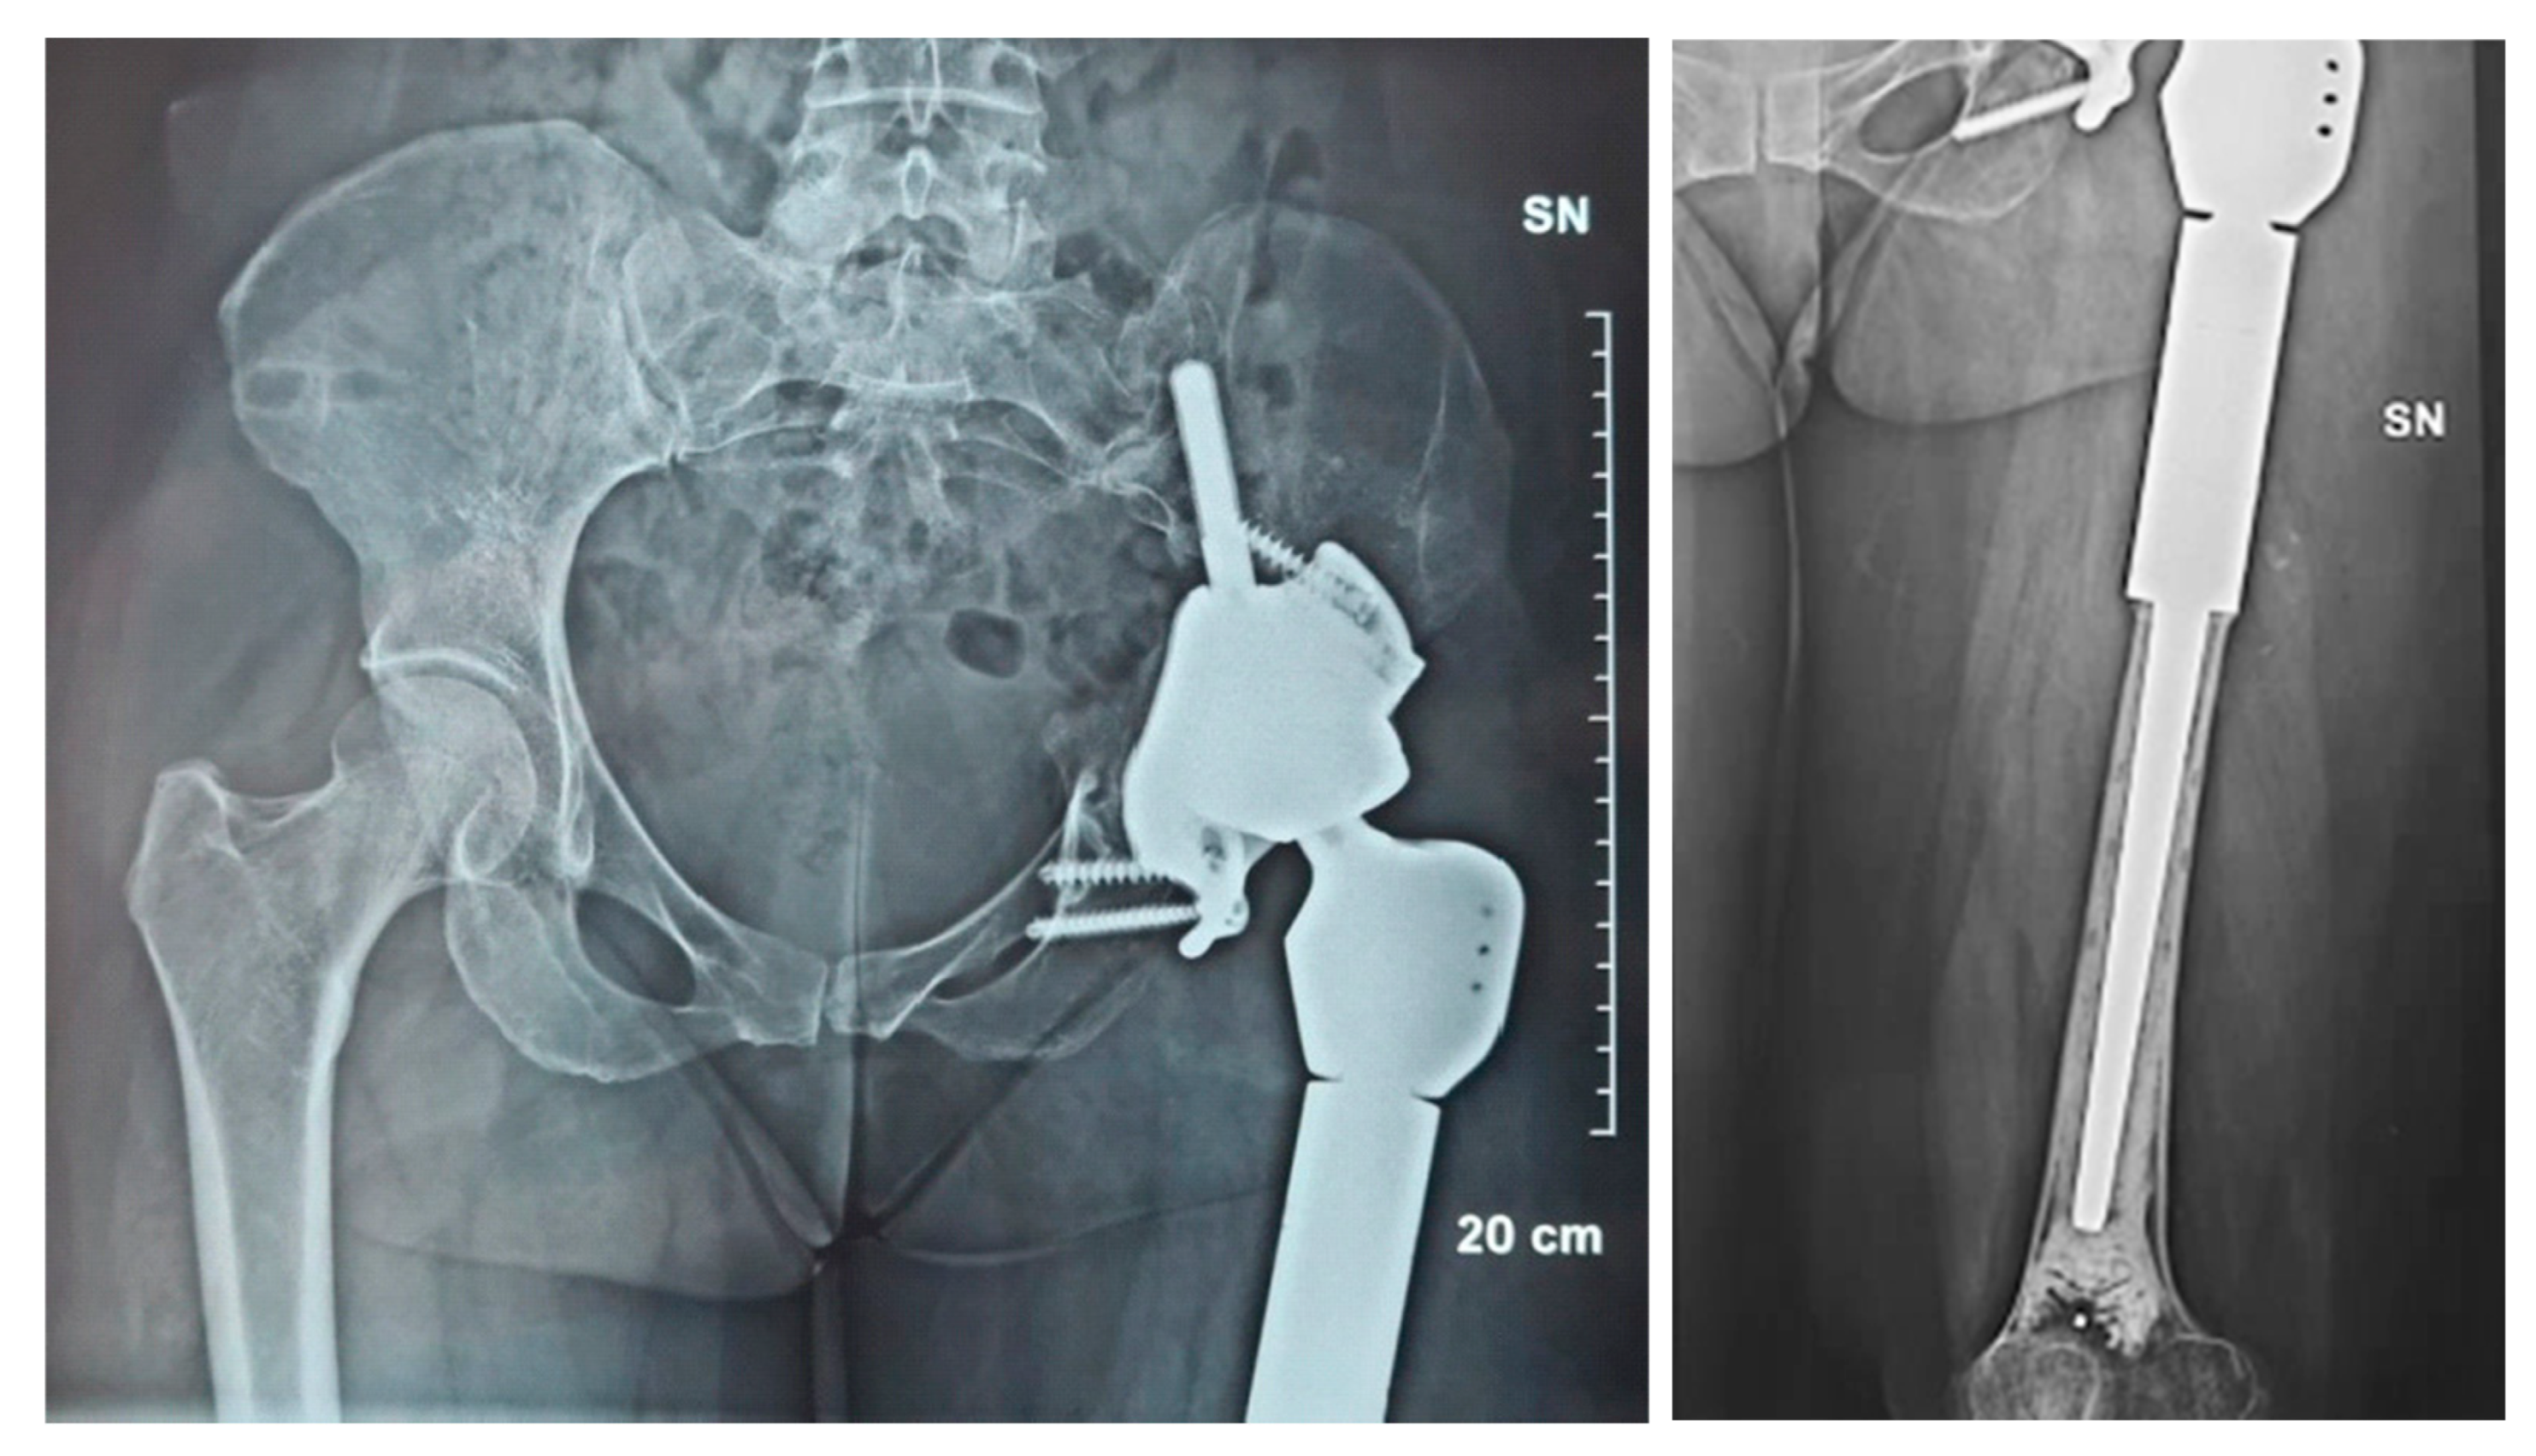

2.1. Case #1

2.2. Case #2